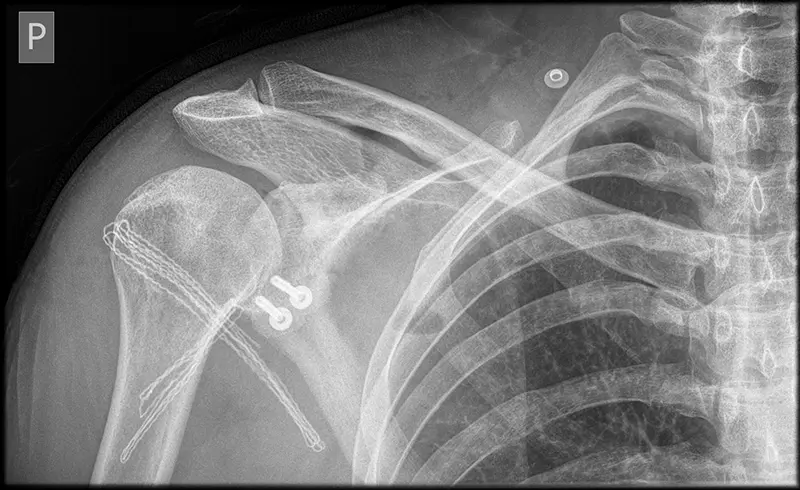

Podstawową zasadą blokady barku jest usunięcie wyrostka kruczego, do którego przyczepione jest ścięgno i więzadło, a następnie opracowanie powierzchni kości i jej przykręcenie do przedniej krawędzi panewki łopatki. Ten proces prowadzi do utworzenia mechanicznej blokady stawu, która zapobiega nadmiernemu ruchowi głowy kości ramiennej w panewce stawowej, co może prowadzić do zwichnięć.

Przykręcanie: Fragment korakoidu (wyrostka kruczego) jest opracowany i przykręcany do panewki łopatki. Istotne jest, aby fragment ten nie wystawał poza brzeg panewki, aby nie kolidował z głową kości ramiennej podczas ruchów barku.

Efekt zaczepu kostnego: Procedura zwiększa średnicę panewki stawowej i tworzy obręcz, która zapobiega podwichnięciu głowy kości ramiennej. Wyrostek kruczy konsoliduje się z panewką, tworząc pojedynczą kość.